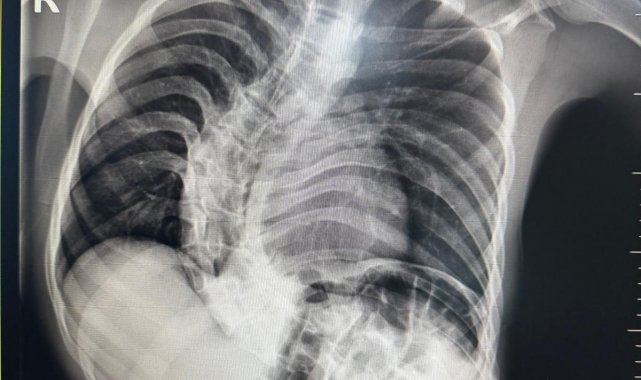

Başarılı geçen ameliyat sonrası hastanın yaşam kalitesinin önemli ölçüde arttığını belirten Ortopedi ve Travmatoloji uzmanı Prof. Dr. Mehmet Atıf Erol Aksekili, skolyoz hakkında bilgi vererek, "Skolyoz kısaca omurganın S şeklini almasıdır. Ön-arka planda omurganın S şeklini almasını biz kısaca skolyoz diyoruz. Skolyoz en sık adolesan dediğimiz ergenlik döneminde görülür. Ancak diğer hastalıklarla birlikte görüldüğünde daha ileri seviyelerde karşımıza çıkabilir. Hastamız 18 yaşında bize başvurdu. Nöromüsküler skolyoz dediğimiz, nörolojik hastalıkların eşlik ettiği bir skolyoz tipi mevcut. Bu skolyozlar erken yaşta ortaya çıkar ve daha hızlı ilerler. Bu yüzden hastamız bize 90 dereceden daha ileri bir seviyede başvurdu" dedi.

Erken teşhis edilmesi halinde daha az cerrahi ile daha iyi sonuç alınabileceğini belirten Aksekili, "Skolyoz erken tanındığında fizik tedavi, egzersiz ve korseleme gibi yöntemlerle ilerlemesini kontrol altına alabiliyoruz. Hastamızda ileri skolyoz olduğu için iki aşamalı cerrahi uygulandı. İlk aşamada Halo Femoral traksiyon yöntemiyle skolyoz kısmen düzeltildi. İkinci aşamada ise vidalar, rodlar ve osteotomi ile omurga düzeltildi" diye konuştu.

Ameliyat sonrası sürecin en az ameliyat kadar önemli olduğuna dikkati çeken Aksekili, omurganın uygun pozisyonda kaynamasının hedeflendiğini belirtti. Hastanın üç ay boyunca dorsolomber korse kullanması gerektiğini söyleyen Aksekili, "Yürümesi öneriliyor ancak ağır yük taşımaması gerekiyor. Yüzme gibi sporlara kısa sürede başlayabilir. Kaynama sürecinde diyetine dikkat etmeli ve 6 hafta ile 3 aylık periyotlarla kontrolleri yapılmalıdır. Kaynama istenilen şekilde ilerlemezse ek müdahaleler veya destek tedavileri uygulanabilir" açıklamasında bulundu.